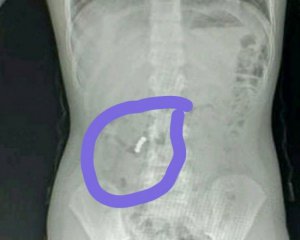

"У нашій школі, в четвертому класі, сталася неприємна ситуація. Дитина проковтнула 4 магнітики, які застрягли в шлунку і почали склеювати внутрішні органи", — сказано в повідомленні.

"Хірург нам сказав, що вони дивом її врятували. У такій ситуації коли потрапляє стороннє тіло за часом є доба, а наша дівчинка ходила з цими магнітами три доби, поки їй не стало погано. Вони пробивають органи, роблячи в них дірки під час тяжіння", — повідомила Марія Смирнова.

До львівської обласної дитячої лікарні Охматдиту потрапив 6-річний хлопчик з болями в животі. При обстеженні лікарі діагностували гострий апендицит. Виявилося, дитина проковтнула кулю для пневматичної гвинтівки.